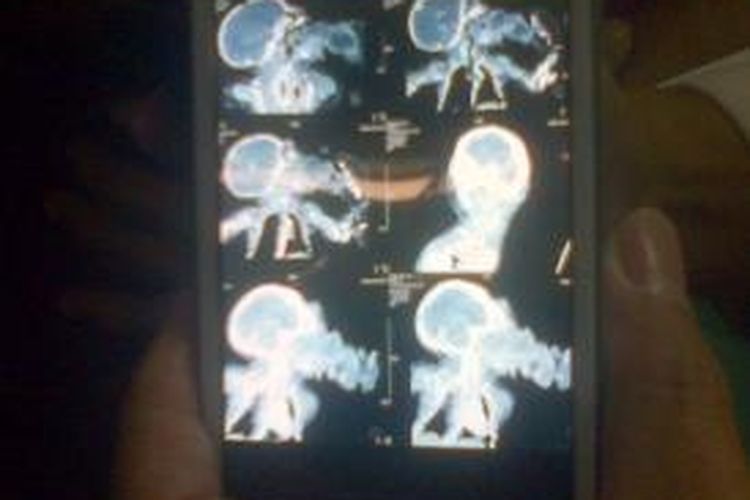

BANDUNG, KOMPAS.com — Operasi pemisahan bayi kembar siam conjoined twin parasitic atau bayi kembar parasit bernama Ginan Septian Nugraha berhasil dilakukan oleh tim khusus penanganan bedah kembar siam Rumah Sakit Hasan Sadikin (RSHS) Bandung.

Operasi pemisahan antara bayi sehat dan bayi parasit yang dalam hal ini disebut sebagai tumor berjenis epicnatus teratoma berlangsung selama tiga jam.

Di tempat yang sama, dokter spesialis bedah anak, Dicky Drajat, menceritakan proses operasi pemisahan tersebut. Dia mengatakan, perlu ketelitian untuk memisahkan antara bayi yang sehat dengan bayi parasit.

Lebih lanjut Dicky menceritakan, bayi parasit yang dapat dikatakan sebagai tumor ini ternyata tidak hanya menempel di langit-lagit mulut, tetapi juga menempel ke lidah bagian kiri hingga ke bawah dan menempel ke rahang.